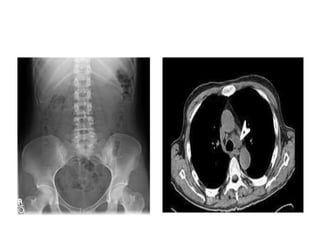

Examples of examinations utilising

contrast agents

• Angiography

• Intravenous urography (IVU),

intravenous pyelography (IVP)

• Computed tomography (CT)

• Interventional techniques

• GI series

• Other examinations